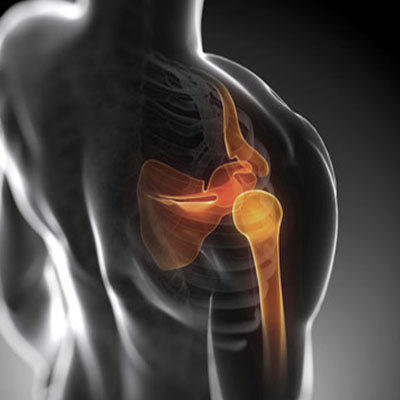

Articulatia umărului

Articulaţia umărului este constituită din trei oase: scapula (omoplatul), humerusul proximal (osul braţului) şi extremitatea externă a claviculei. Capul humeral are forma unei bile şi se articulează cu o scobitură a scapulei numită glenă.